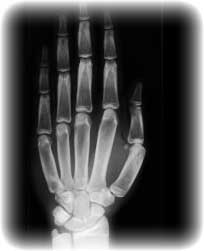

X-Ray

Probably the most common diagnostic imaging tool available, an X-ray is a simple, painless procedure. An X-ray is performed by focusing low levels of radiation into a beam that passes through the body, strikes a photographic film, and produces a picture. Extremity X-rays of the hand, arm, wrist, foot, ankle or head, for example, can be performed for a variety of reasons:

• To determine the cause of pain

• To evaluate a fractured or dislocated bone

• To evaluate an injury or damage caused by a condition such as arthritis or osteoporosis